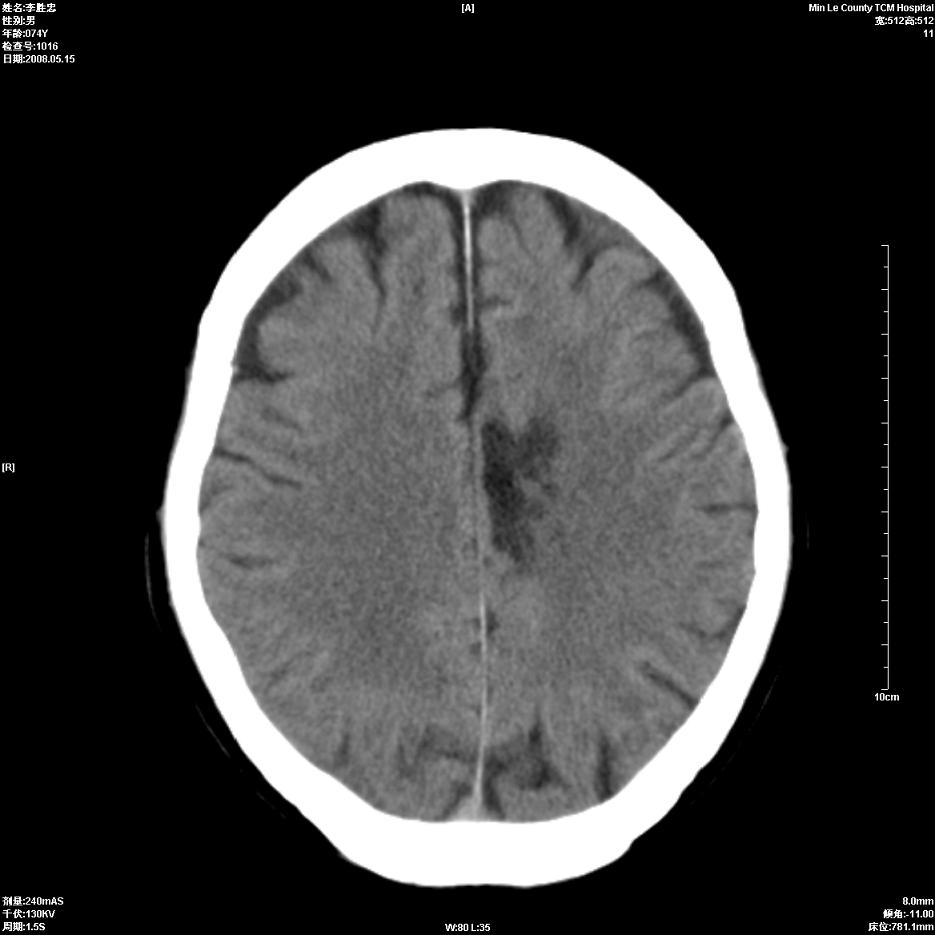

以下是引用hhcckk在2008-5-30 14:26:00的发言:[br]病灶跨中线,有占位效应,强化不明显,考虑胼胝体区低级别的星形细胞瘤可能性大,建议mr检查